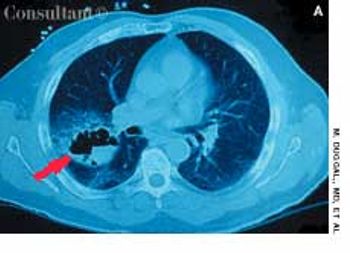

A 25-year-old man, who was an injection drug user, presented with a several-day history of dyspnea and fever. He complained of excessive malaise, fatigue, and weight loss but denied any hemoptysis. The examination of the lung revealed bilateral crackles in both lower zones.